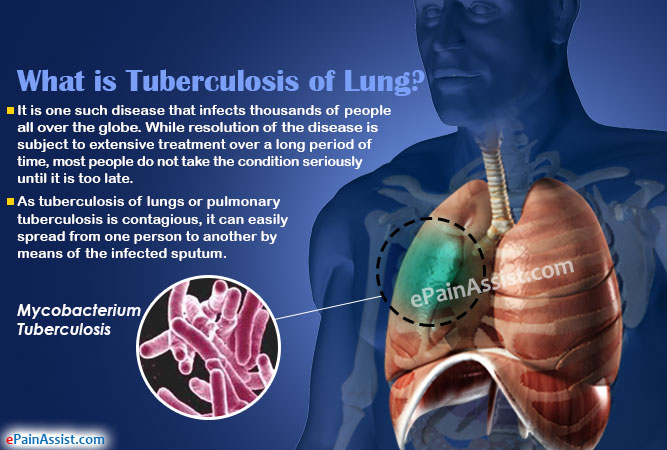

4. Pulmonary Tuberculosis:

The lungs lose their elasticity and are unable to allow gaseous exchange. It is caused by bacteria. Sufferers experience prolonged cough and pains.

4. Pulmonary Tuberculosis:

The lungs lose their elasticity and are unable to allow gaseous exchange. It is caused by bacteria. Sufferers experience prolonged cough and pains.